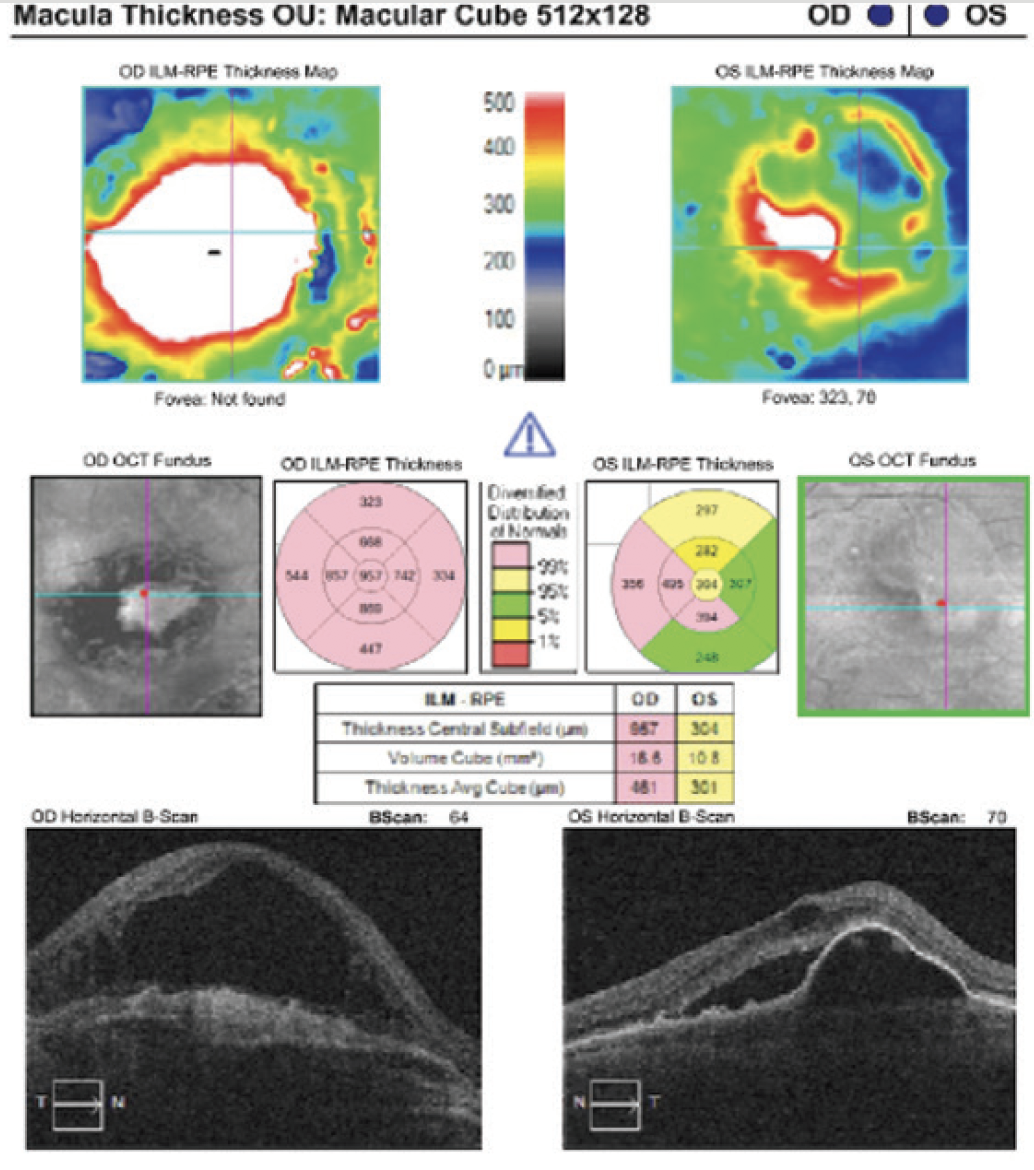

- Initial visit imaging showed active exudative neovascular AMD OS and a large disciform scar OD (Figure 1)

Figure 1. Baseline imaging in an 86-year-old woman referred for anti-VEGF agent switch.